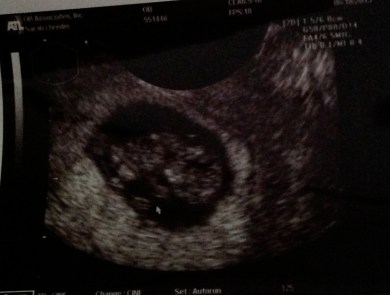

I saw the first photos of our first grandchild the other day, and it was a profoundly spiritual experience.

Image

Baby Schroeder…beloved child.